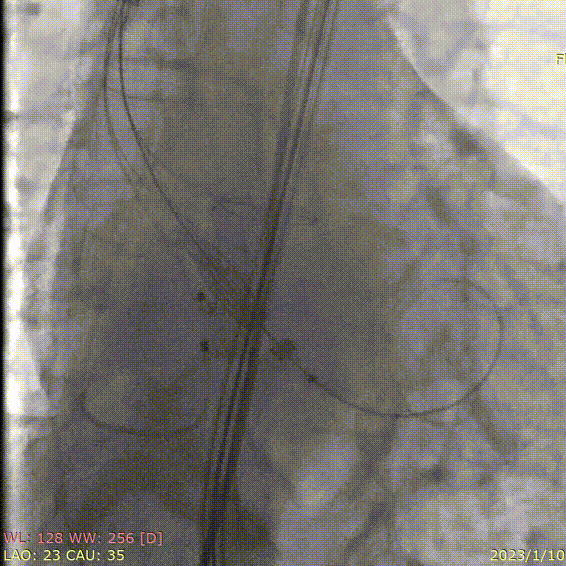

术前造影

定位件入窦

释放瓣膜

术后造影